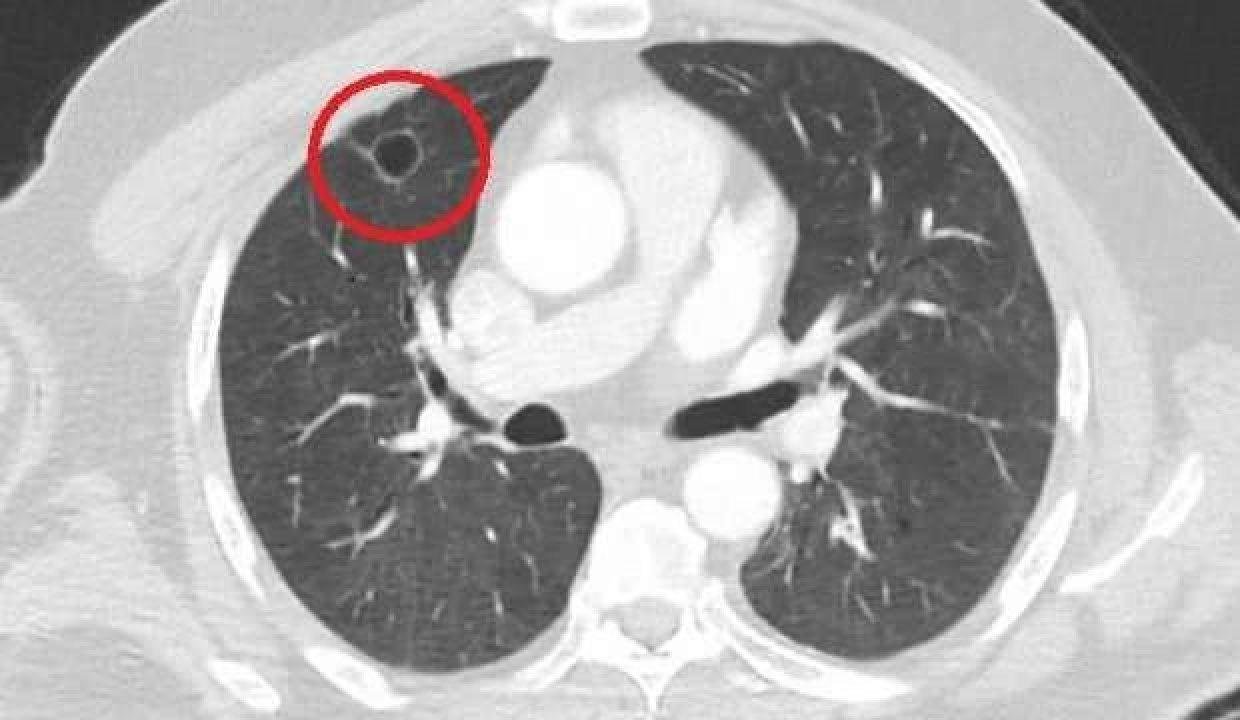

Kent dışında çalışan N.T.'nin, göğüs ağrısı şikayetiyle gittiği hastanede çekilen tomografisinde sağ akciğerinde 4 santimetre çapında tümör ...

Akciğer kanseri, akciğer dokularından kaynaklanan bir kanser türüdür. Akciğer kanseri insidansı dünya çapında istikrarlı bir şekilde artmakta ve ...

Akciğer kanseri, akciğer dokularındaki hücrelerin kontrolsüz çoğaldığı bir hastalıktır. Son zamanlarda ülkemizde ve tüm dünyada artan kanserlerin ...